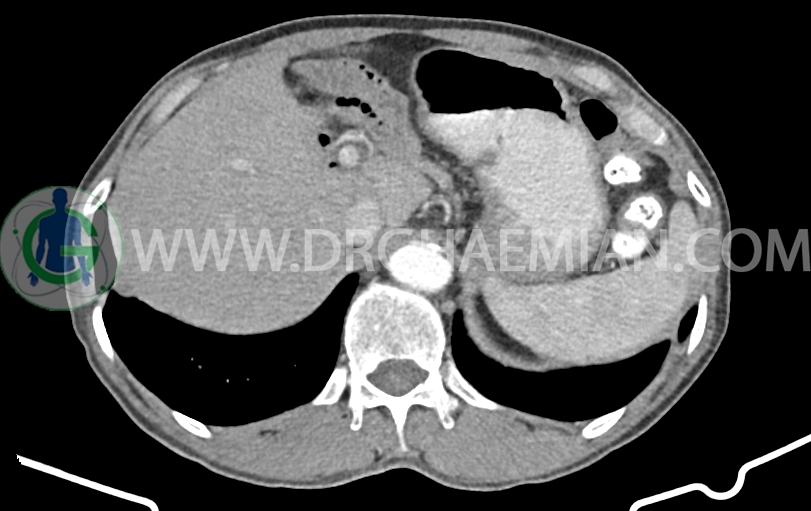

شواهد جراحی ویپل به صورت partial pancratectomy و کوله سیستکتومی و همچنین گاستروژژنوستومی و پانکراتیکوژژنوستومی – هپاتوژژنوستومی مشهود است .

کانون کلسیفیه کوچک فاقد اهمیت بالینی در لوب راست کبد رویت شد

پنوموبینی در لوب چپ کبد مشهود است.

افزایش ضخامت ناحیه کاردیا مشاهده می شود )تطبیق با اندوسکوپی)

MPD دیلاته به قطر 8mm (حاوی استنت می باشد)

body پانکراس کمی کوچک و اتروفیک است